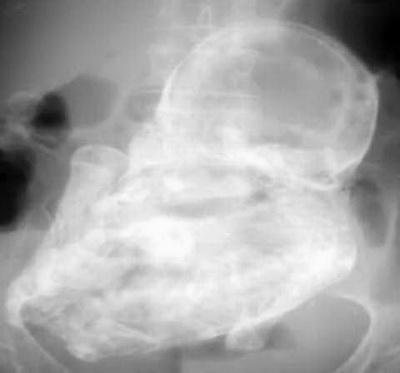

нарийвчилсан шинжилгээ хийтэл рентген зургаар том хавдар мэт зүйл илэрсэн

байна.

Гэтэл эмэгтэй тээсэн ургаа 40 жил гаргалгүй явсаар ураг нь бараг л

чулуужсан юм шиг болсон байх нь тэр. “Эмнэлгийн практикт давсганд чулуу үүсэх

тохиолдол олон. Харин энэ удаа маш ховор тохиолдол таарлаа. Энэ бол савны

гадуур жирэмсэлсэн тохиолдол. Исавны гадуурх ураг ихэнх тохиолдолд үхдэг.

Ингээд л 42 насандаа жирэмсэлсэн эмэгтэйн хөврөл 40 жил гэдсэнд нь байхдаа

бараг чулуужсан нь энэ” гэж эмч нар хэлжээ. Ингээд эмээ энэ ургаа авхуулахаар